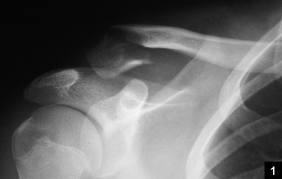

# كسور الطرف العلوي لعظم العضد: نظرة شاملة ## مقدمة تعتبر كسور الطرف العلوي لعظم العضد من الإصابات الشائعة، خاصة بين …

# كسور عظم العضد القريب: الانتشار، الأسباب، التشخيص، والعلاج تُعد كسور عظم العضد القريب من الإصابات الشائعة، خاصةً بين ك…